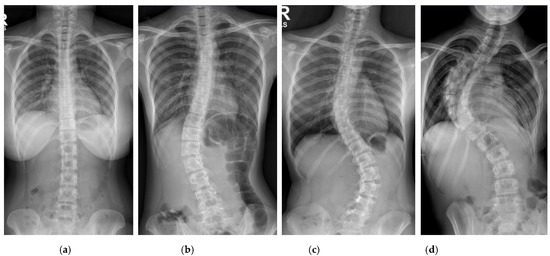

The center offset and corner offset maps using convolutional layers for landmark localization were constructed. Since the output of the feature map on the network is downsized, the center offset and corner offset are mapped to a new location which is then trained with L1 loss. Detection bounding boxes were displayed on each vertebra after applying the object detection step on the X-ray images. The coordinates for the corners and center of each bounding box were found as presented in Figure 6.

Figure 6.

Progressive results of the vertebrae detection to get the location of 4 corners and a center.